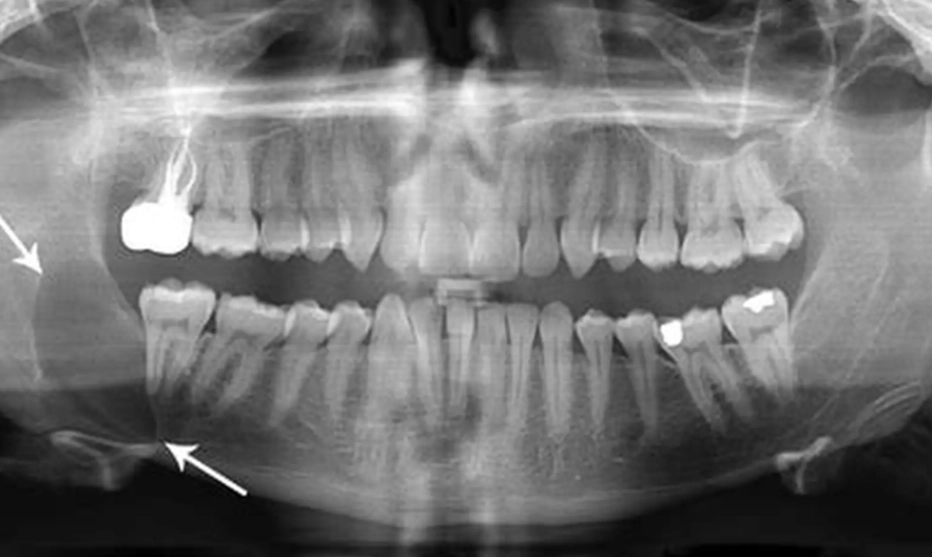

1. Panoramic X-ray (OPG): This is the first and most common step. It gives a broad view of both jaws, all teeth, and the sinuses. A cyst appears as a well-defined, dark (radiolucent) area around the crown of the impacted wisdom tooth, often with a thin white border. It looks like a dark halo.

A common mistake I see is dentists planning surgery based solely on a 2D X-ray. Without a 3D scan, you're essentially navigating in the dark. You might not know the cyst is wrapped around the nerve until you're in the middle of the procedure, which increases the risk of nerve injury.